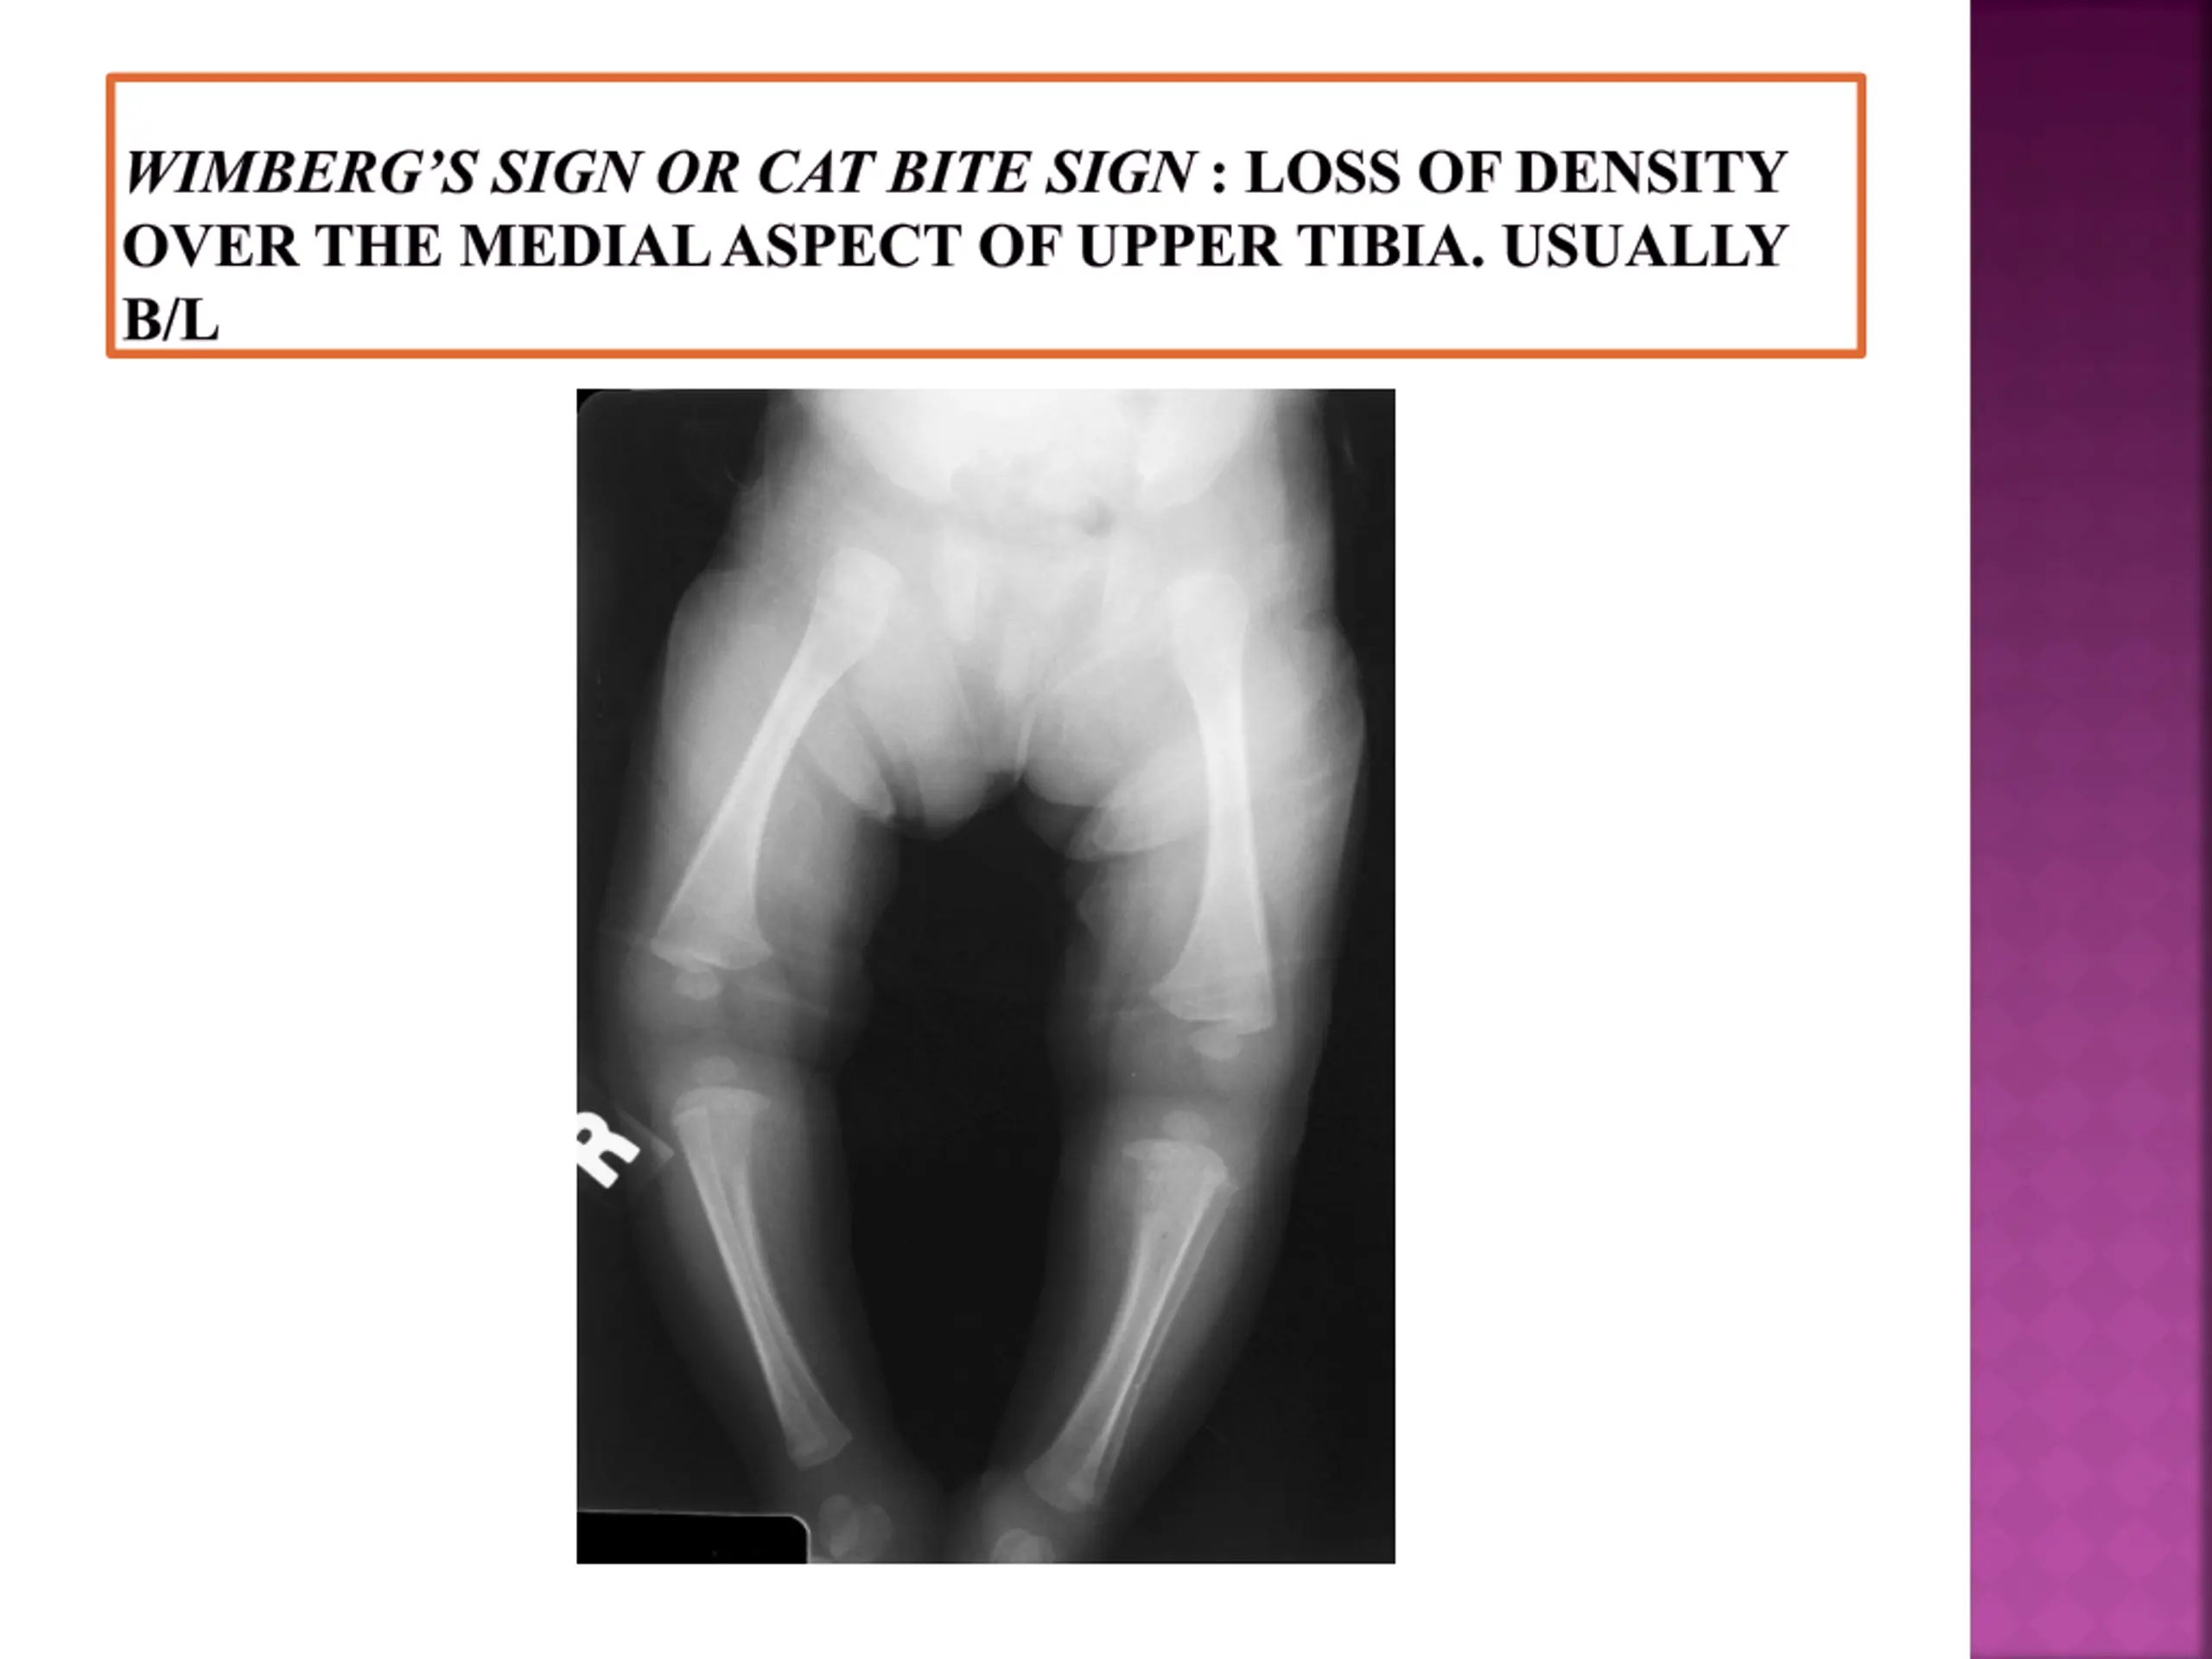

WIMBERGS SIGN OR CAT BITE SIGN : LOSS OF DENSITY OVER THE MEDIAL ASPECT OF UPPER TIBIA. USUALLY B/L